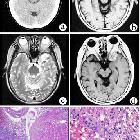

Multicystic

meningioangiomatosis. Axial brain magnetic resonance imaging (MRI) findings. A multicystic mass (arrow) with low signal intensity on T1-weighted images (A) and high signal intensity on T2-weighted images (B) is seen in the right temporal lobe. The cystic component was isointense with the cerebrospinal fluid on all sequences.